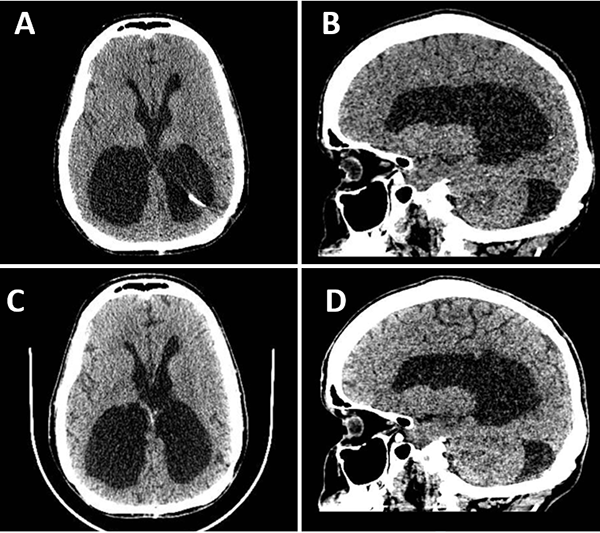

Una vez retirado el segmento migrado, se colocó un nuevo catéter distal en el atrio. Luego del procedimiento, la paciente presentó franca mejoría sintomática con resolución del cuadro de cefalea y Parinaud. Se realizó una tomografía de control a los dos días en donde se corroboró la disminución del volumen del sistema ventricular y fue dada de alta deambulando por sus propios medios. En el control ambulatorio, al mes de la cirugía, se mantuvo asintomática, sin nuevos signos de hidrocefalia ni complicaciones asociadas, con un control imagenológico estable (Figura 4).

Figura 4. A y B. Corte axial y sagital de TC de cerebro en segundo día postoperatorio, evidenciándose franca disminución del volumen del sistema ventricular. C y D. Corte axial y sagital de TC de cerebro control al mes de la cirugía, sin cambios.